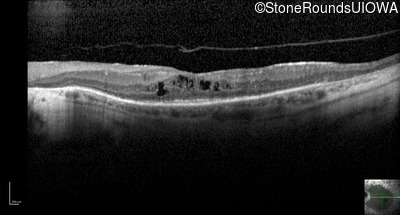

Optical Coherence Tomography - Right - 20/63 -1

Exemplar / OCT Stack